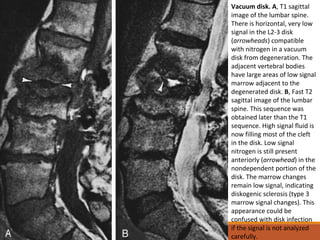

Vacuum disk. A, T1 sagittal

image of the lumbar spine.

There is horizontal, very low

signal in the L2-3 disk

(arrowheads) compatible

with nitrogen in a vacuum

disk from degeneration. The

adjacent vertebral bodies

have large areas of low signal

marrow adjacent to the

degenerated disk. B, Fast T2

sagittal image of the lumbar

spine. This sequence was

obtained later than the T1

sequence. High signal fluid is

now filling most of the cleft

in the disk. Low signal

nitrogen is still present

anteriorly (arrowhead) in the

nondependent portion of the

disk. The marrow changes

remain low signal, indicating

diskogenic sclerosis (type 3

marrow signal changes). This

appearance could be

confused with disk infection

if the signal is not analyzed

carefully.